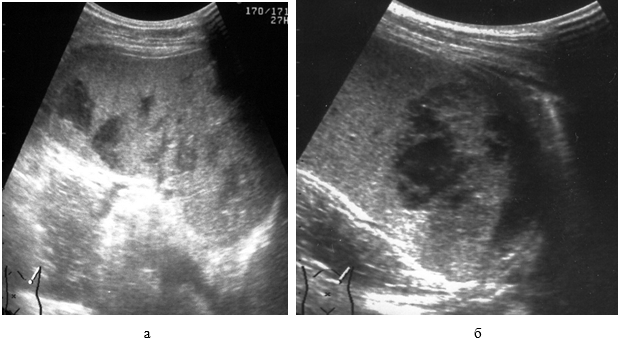

Интрапаренхиматозная гематома. Селезенка увеличена в размерах, деформирована. При компьютерной томографии в пульпе определяются неправильной формы поля патологической денситометрии, которые в острой и подострой стадиях могут быть хорошо визуализированы только после внутривенного усиления. В более поздние сроки формирования гематомы это возможно без дополнительного введения контраста. Гематома имеет неровные края и иногда проявляется в виде «обрывков ткани» (рис. 16).

Рис. 16. КТ-признаки интрапаренхиматозной гематомы селезенки через 9 суток после травмы:

а – нативное сканирование; б – после внутривенного усиления. 1 – гематома (28 ± 5 ед. Н).